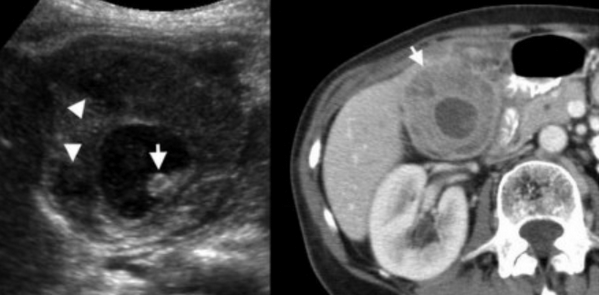

Ксантогранулематозный холецистит — это воспалительное заболевание, характеризующаяся тем, что в стенке желчного пузыря образуются ксантомы и гранулемы. При исследовании выявляют утолщение стенки желчного пузыря, уменьшение органа в размере, а также интрамуральные узелки, которые визуализируются, как гипоэхогенные включения на УЗИ и гиподенсные на компьютерной томограмме. Данные включения схожи с включениями при карциноме желчного пузыря.

УЗИ и КТ желчного пузыря. Ксантогранулематозный холецистит. Слева на УЗИ визуализируется (помечено стрелками) утолщение стенки желчного пузыря с интрамуральным включением и с камнем в просвете органа. Справа на КТ выявляется утолщение стенки с гиподенсными включениями.

УЗИ (слева) и КТ (справа) желчного пузыря. На УЗИ ярко выраженное утолщение стенки желчного пузыря (указаны белыми стрелками). Множественные камни в просвете желчного пузыря (указано стрелкой). Компьютерная томография с контрастным усилением. На КТ визуализируются утолщение стенки с внутристеночными гиподенсными включениями. На КТ также выявлено, что процесс распространился на печень (указано стрелкой).